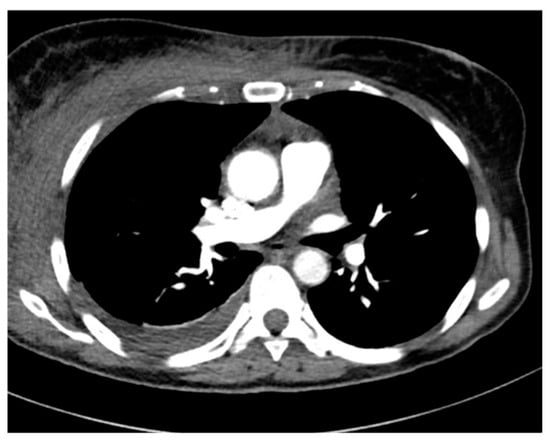

| 6 | 49/F | Pneumonia Pleural empyema | Type 2 Diabetes Mellitus | no | 9 | 3 | no | 58 days | Discharge |

| 6 | No | pleural drainage | pleural fluid | Ceftriaxone Metronidazole | Penicillin Clindamicin |